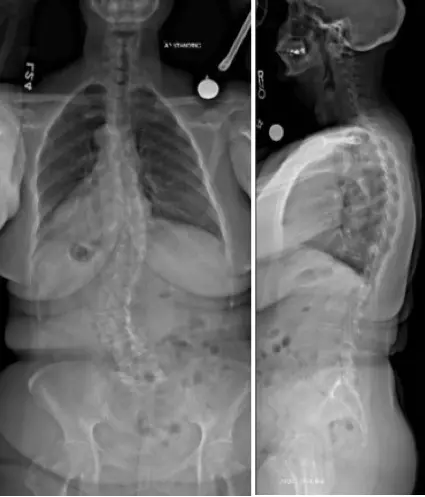

Diagnosis: Degenerative scoliosis with significant multilevel degeneration of the joints and severe nerve compression

“The magnetic resonance imaging (MRI) showed severe narrowing of the bony channels where the nerves leave the spine and travel to the legs for sensation and strength. This narrowing correlated with her symptoms and clinical presentation,” says Smith.

scoliosis2